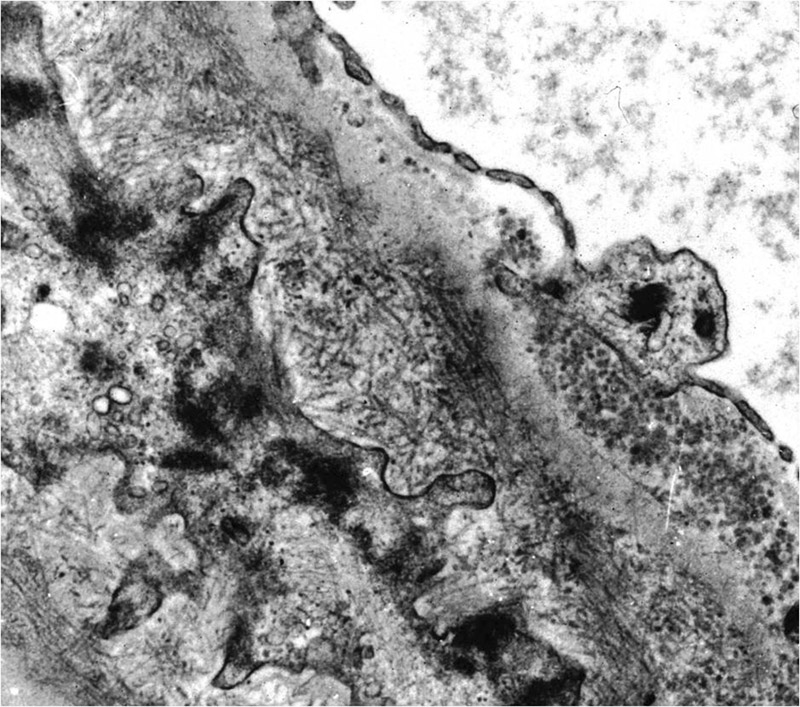

In 1977 Rosenmann and Eliakim described a glomerulopathy with amyloid-like fibrillary material which did not stain with Congo red [1]. Following this publication, there were a few similar case reports [2–6]. According to the criteria of Rosenstock [7] FGN is characterised by randomly arranged fibrillary deposits with a diameter of less than 30 nm (fig. 1). No hollow centres should be identifiable at magnifications of less than 30,000x. Congo-red staining has to be negative, while the immunofluorescence for immunoglobulines has to be positive. Deposits are often polyclonal and mostly made up of IgG4 in contrast to immunotactoid glomerulopathy (IT) in which deposits are almost always monoclonal and do not contain Ig4. FGN is a rare disease diagnosed in about 0.6 to 1% of all native kidney biopsies [7–10]. FGN has to be distinguished from IT, which likely represents a different clinical and pathologic entity [8, 11, 12]. FGN is usually not associated with monoclonal gammopathy or lymphoproliferative disorder.

Figure 1

Electron microscopy: peripheral basement membrane with randomly arranged fibrillary deposits.